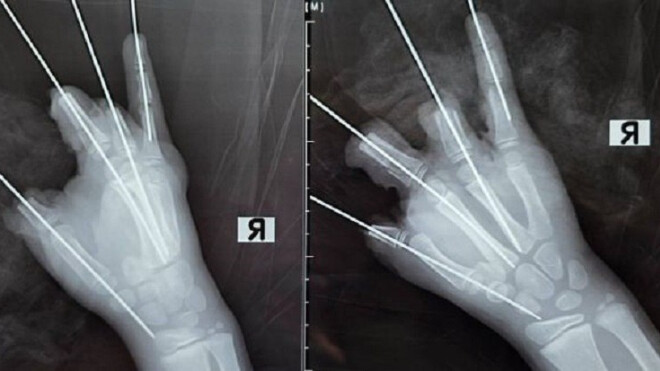

Как рассказали в Педиатрическом университете, взрыв петарды привёл к ампутации четырёх пальцев с большого по безымянный и серьёзным повреждениям мизинца, а также к открытым переломам и вывиху пястной кости. Мягкие ткани кисти сильно повреждены.

Ребёнка срочно доставили в клинику Педиатрического университета, где врачи незамедлительно провели сложную пятичасовую операцию. Детский микрохирург отметил, что часть тканей сохранить удалось, но реконструировать кисть полностью невозможно из-за серьёзности травмы.